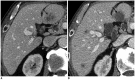

Tumor response may be assessed readily by the use of Response Evaluation Criteria in Solid Tumor version 1.1. However, the criteria mainly depend on tumor size changes. These criteria do not reflect other morphologic (tumor necrosis, hemorrhage, and cavitation), functional, or metabolic changes that may occur with targeted chemotherapy or even with conventional chemotherapy. The state-of-the-art multidetector CT is still playing an important role, by showing high-quality, high-resolution images that are appropriate enough to measure tumor size and its changes. Additional imaging biomarker devices such as dual energy CT, positron emission tomography, MRI including diffusion-weighted MRI shall be more frequently used for tumor response evaluation, because they provide detailed anatomic, and functional or metabolic change information during tumor treatment, particularly during targeted chemotherapy. This review elucidates morphologic and functional or metabolic approaches, and new concepts in the evaluation of tumor response in the era of personalized medicine (targeted chemotherapy).